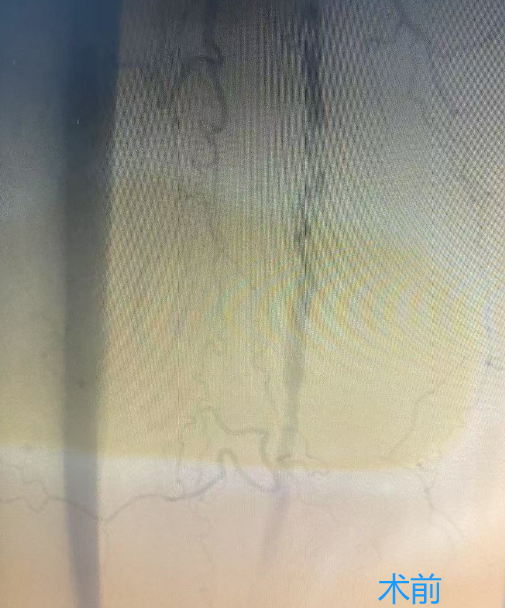

下肢动脉硬化闭塞症的治疗方式包括:生活方式调整、药物治疗、血管腔内治疗、外科手术和康复等方法,可有效缓解症状,提升生活质量。特别是下肢动脉旋切术,作为微创技术,能有效清除血管壁上的斑块。

下肢动脉旋切术的优势

1、无需植入支架:降低了远期并发症的发生率,如血栓和再狭窄等。

2、创伤小,恢复快:减轻了手术痛苦,加速了术后恢复,使患者能迅速回归日常生活。

3、治疗效果显著:改善下肢动脉闭塞,恢复血流畅通,缓解疼痛,提高生活质量。

葫芦岛市第二人民医院血管介入病区现已常规开展下肢动脉旋切术,标志着我市周围血管疾病微创技术及相关领域诊疗水平迈上了新台阶。这一技术的广泛应用,结合先进的影像技术,将为更多下肢动脉疾病患者带来福音,让他们重获健康与希望。